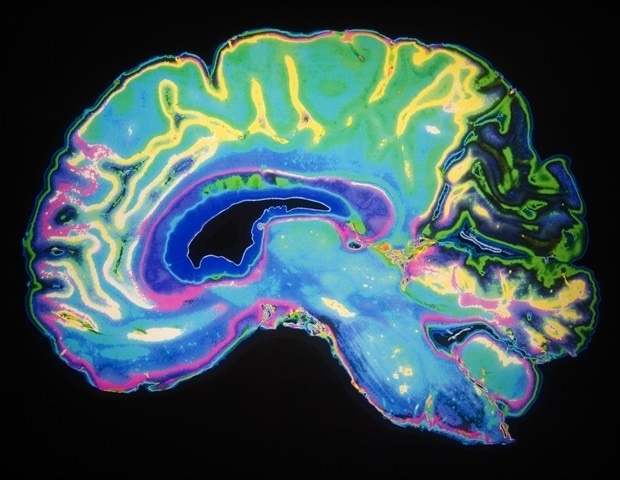

A study led by Georgetown University neuroscientists reveals that the part of the brain that receives and processes visual information in sighted people develops a unique connectivity pattern in people born blind. They say this pattern in the primary visual cortex is unique to each person -; akin to a fingerprint.